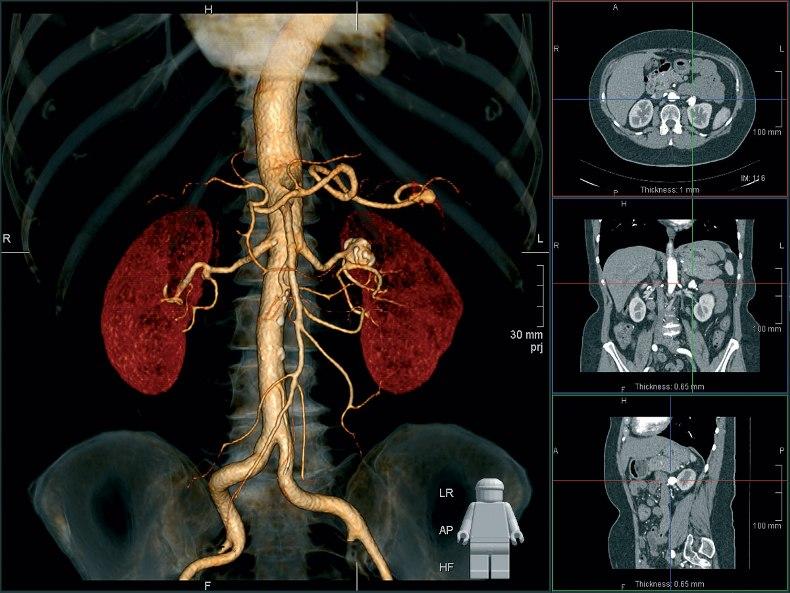

Компьютерная томография (КТ)

Компьютерная томография тоже осуществляется по принципу рентгенографии, но в результате врач получает не плоскую двухмерную картинку, а трёхмерное изображение. Это достигается путём одновременного создания большого числа снимков, которые собираются в единое изображение. Датчики компьютерного томографа обладают высокой чувствительностью и различают огромное количество оттенков, поэтому врач может детально рассмотреть все кости и органы пациента. Дополнительно повысить качество изображения можно, если ввести пациенту специальное вещество, так называемый “контраст”. Контраст помогает отличить здоровые ткани от изменённых и обнаружить аномальные структуры в организме, а также даёт возможность детально изучить состояние сосудов. КТ с контрастом назначают не в каждом случае, часто достаточно простой компьютерной томографии.

КТ делается быстро, с его помощью проводить скрининг на рак лёгких. Также можно использовать компьютерную томографию непосредственно во время проведения хирургических операций.

Недостатками КТ можно считать высокую лучевую нагрузку на пациента. Поэтому КТ не назначают беременным женщинам, детям и пациентам с избыточным весом (более 200 килограмм).

снимок кт